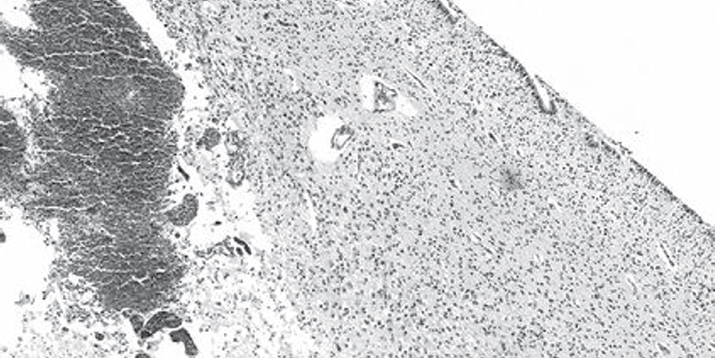

Микроскопическое исследование вентрикулярной и перивентрикулярной области головного мозга показало нарушение целостности эпендимы, в норме образующей достаточно тонкий ровный слой кубических клеток. Так, в исследуемой области эпендима представляла собой неоднородный слой клеток, местами наслаивающихся друг на друга. В отдельных участках отмечена десквамация эпендимоцитов в просвет желудочков. В проекции герминативного матрикса обнаружена густая сеть кровеносных сосудов микроциркуляторного русла (рис. 1).

Рис. 1. Густая сеть кровеносных сосудов микроциркуляторного русла в проекции герминативного матрикса. Окраска гематоксилином и эозином. Ув. ×40 / Fig. 1. A vascular network of the microvasculature of the germinal matrix (H&E stain). Magnification ×40

На микрофотографии видны сосуды микроциркуляторного русла, имеющие разный размер и форму, располагающиеся небольшими группами и по отдельности. Просвет большей части сосудов расширен и заполнен форменными элементами крови с преобладанием эритроцитов. Кроме этого, визуализируются единичные, извилистой формы, спавшиеся неполнокровные кровеносные сосуды. Выстилка сосудов микроциркуляторного русла представлена эндотелием, располагающимся преимущественно в один ряд; местами, в части изгиба сосуда, отмечается наложение друг на друга эндотелиальных клеток. Большая часть эндотелиоцитов овальные, другие чуть вытянутой формы, располагающиеся в отношении друг друга не плотно, межклеточные контакты широкие. В отдельных кровеносных сосудах отмечается слущивание эндотелия с дефектом сосудистой стенки и выходом форменных элементов крови во внесосудистое пространство. Кисты, определяющиеся преимущественно на границе герминативного матрикса с белым веществом головного мозга, формировались скорее всего в результате деструктивного отека и характеризовались образованием полостей вокруг сосуда. В отдельных участках вещества головного мозга перивентрикулярной области определяются диффузные кровоизлияния с очагами геморрагических некрозов и пропитыванием кровью ткани субэпендимального пространства (рис. 2).